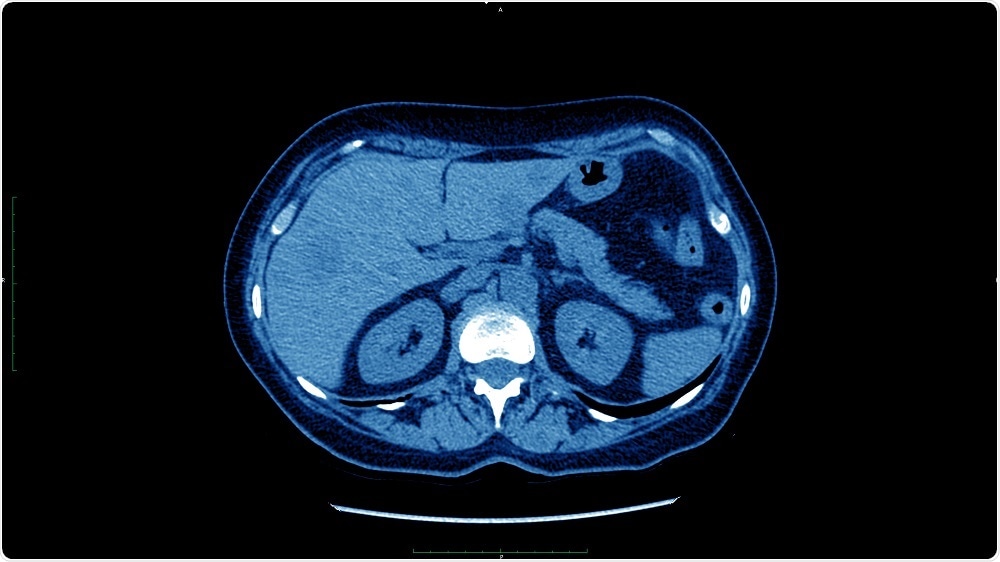

Credit: dade72/Shutterstock.com